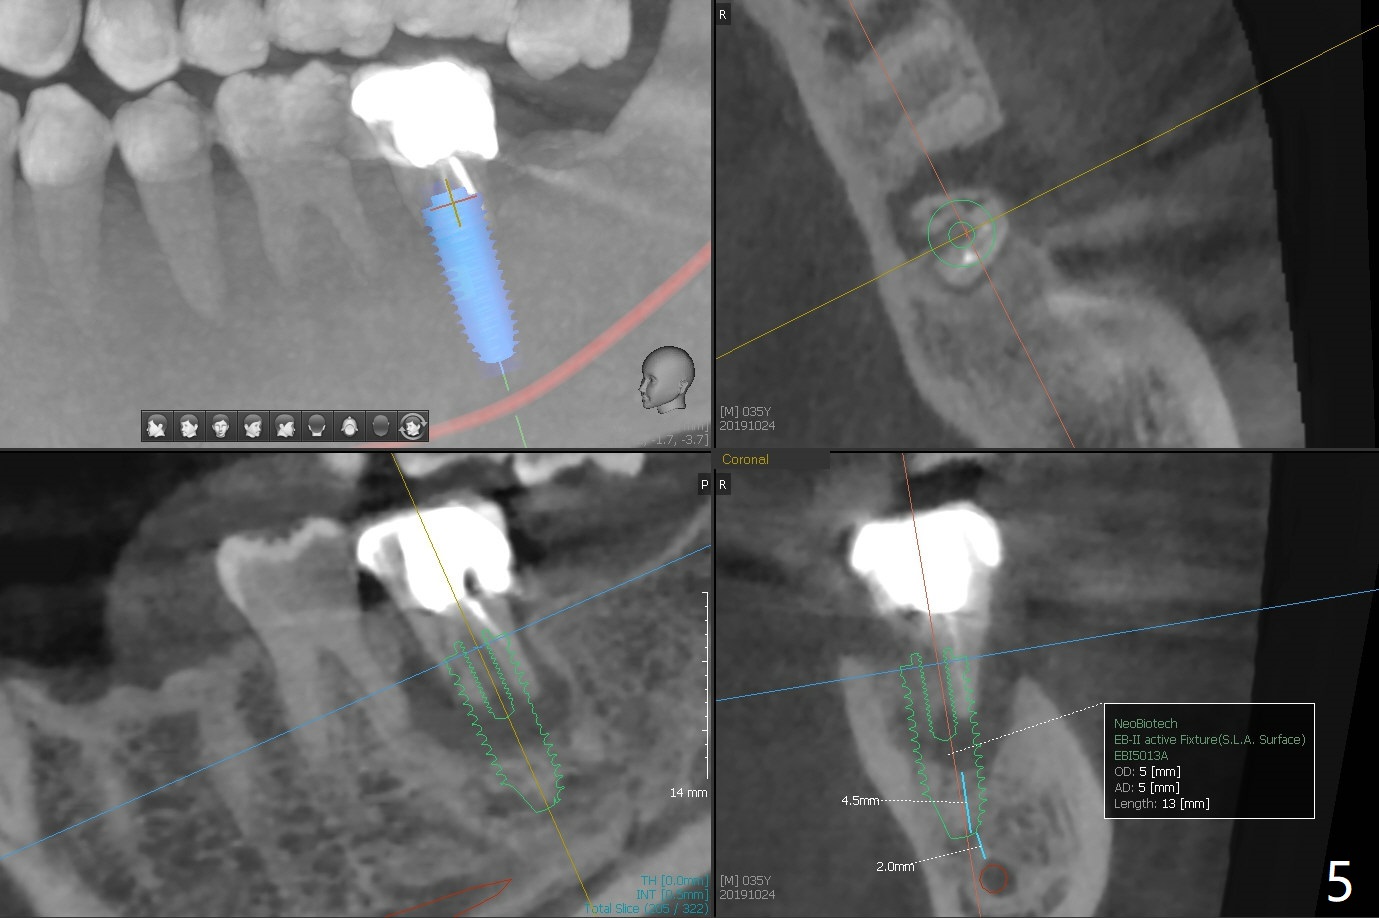

Mesial Root Fracture

A 35-year-old man has repeated pain at #18 (Fig.1). He is a bruxer with exostosis (Fig.2 *). It appears that the mesial root of the affected tooth has vertical fracture (Fig.1-4). A 5x11.5 or 13 mm implant is appropriate (11 or 13 mm FC, Fig.5). Draw blood for PRFx2/sticky bone.